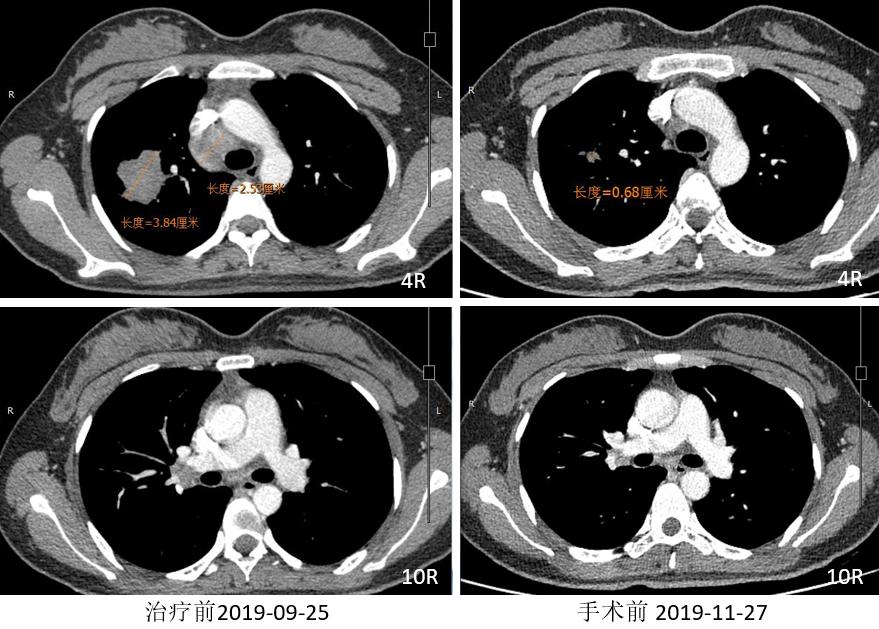

胸部CT

外周淋巴结CT